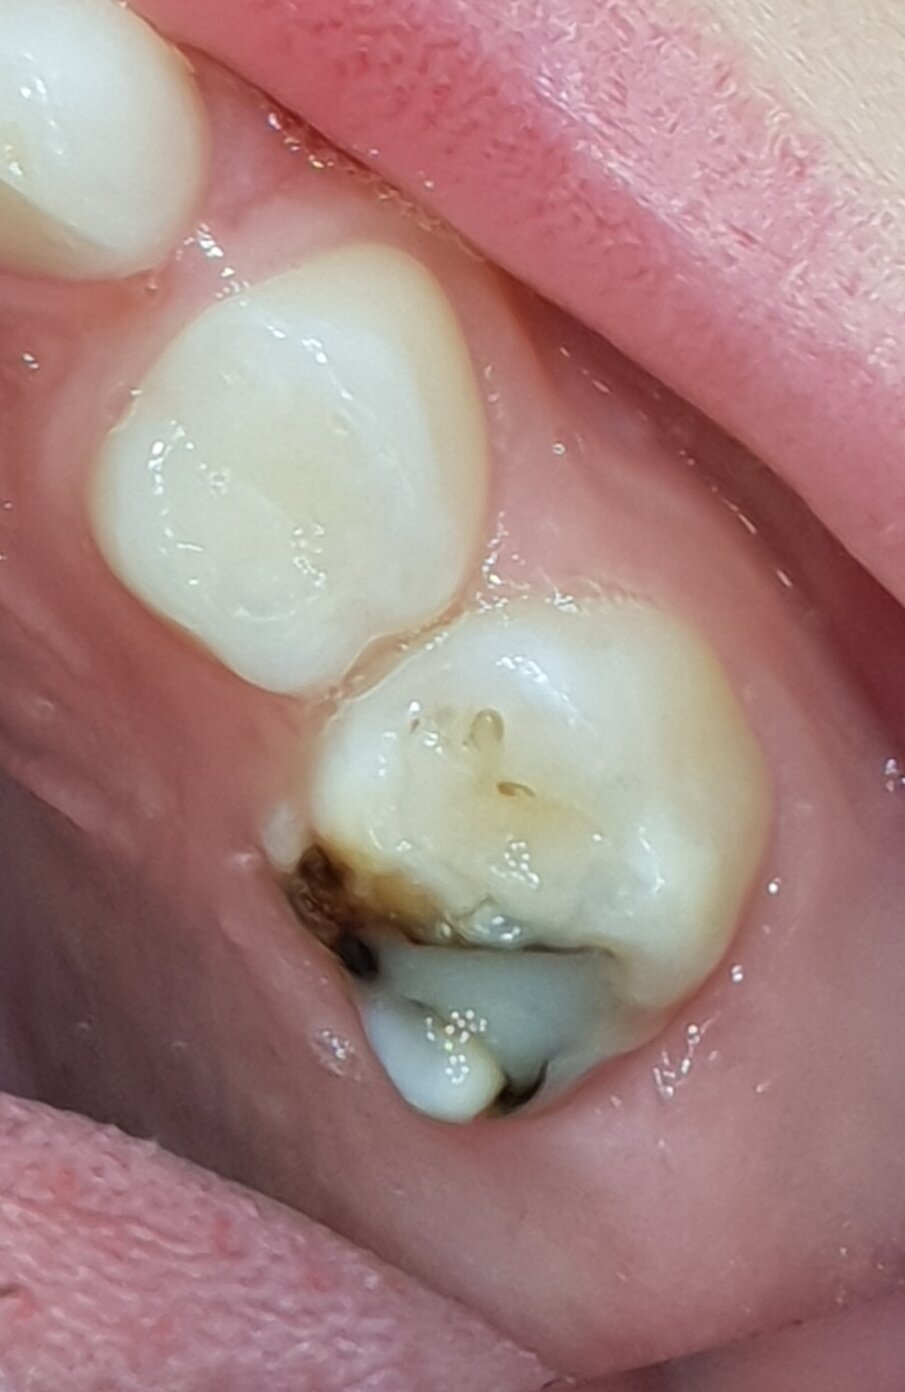

Een kind van vierenhalf jaar met multi-cariës werd verwezen voor behandeling onder narcose (afb. 6a-e). Klacht: lichte gevoeligheid .

Bij deze eerste sessie trainde ik het poetsen, opende ik de laesies voorzichtig en behandelde de laesies met SDF. Bij het monitoren zal blijken of er aanvullende behandelingen nodig zijn zoals herhalen SDF, SMART, Hall-kroon of lokaal een conventionele behandeling.

Afbeelding 6d. Cariëslaesies vrijgelegd en SDF aangebracht. Evaluaties van de zelfzorg bepalen de balans tussen causale therapie en symptoombestrijding.

Afbeelding 6e. Cariëslaesies vrijgelegd en SDF aangebracht. Evaluaties van de zelfzorg bepalen de balans tussen causale therapie en symptoombestrijding.